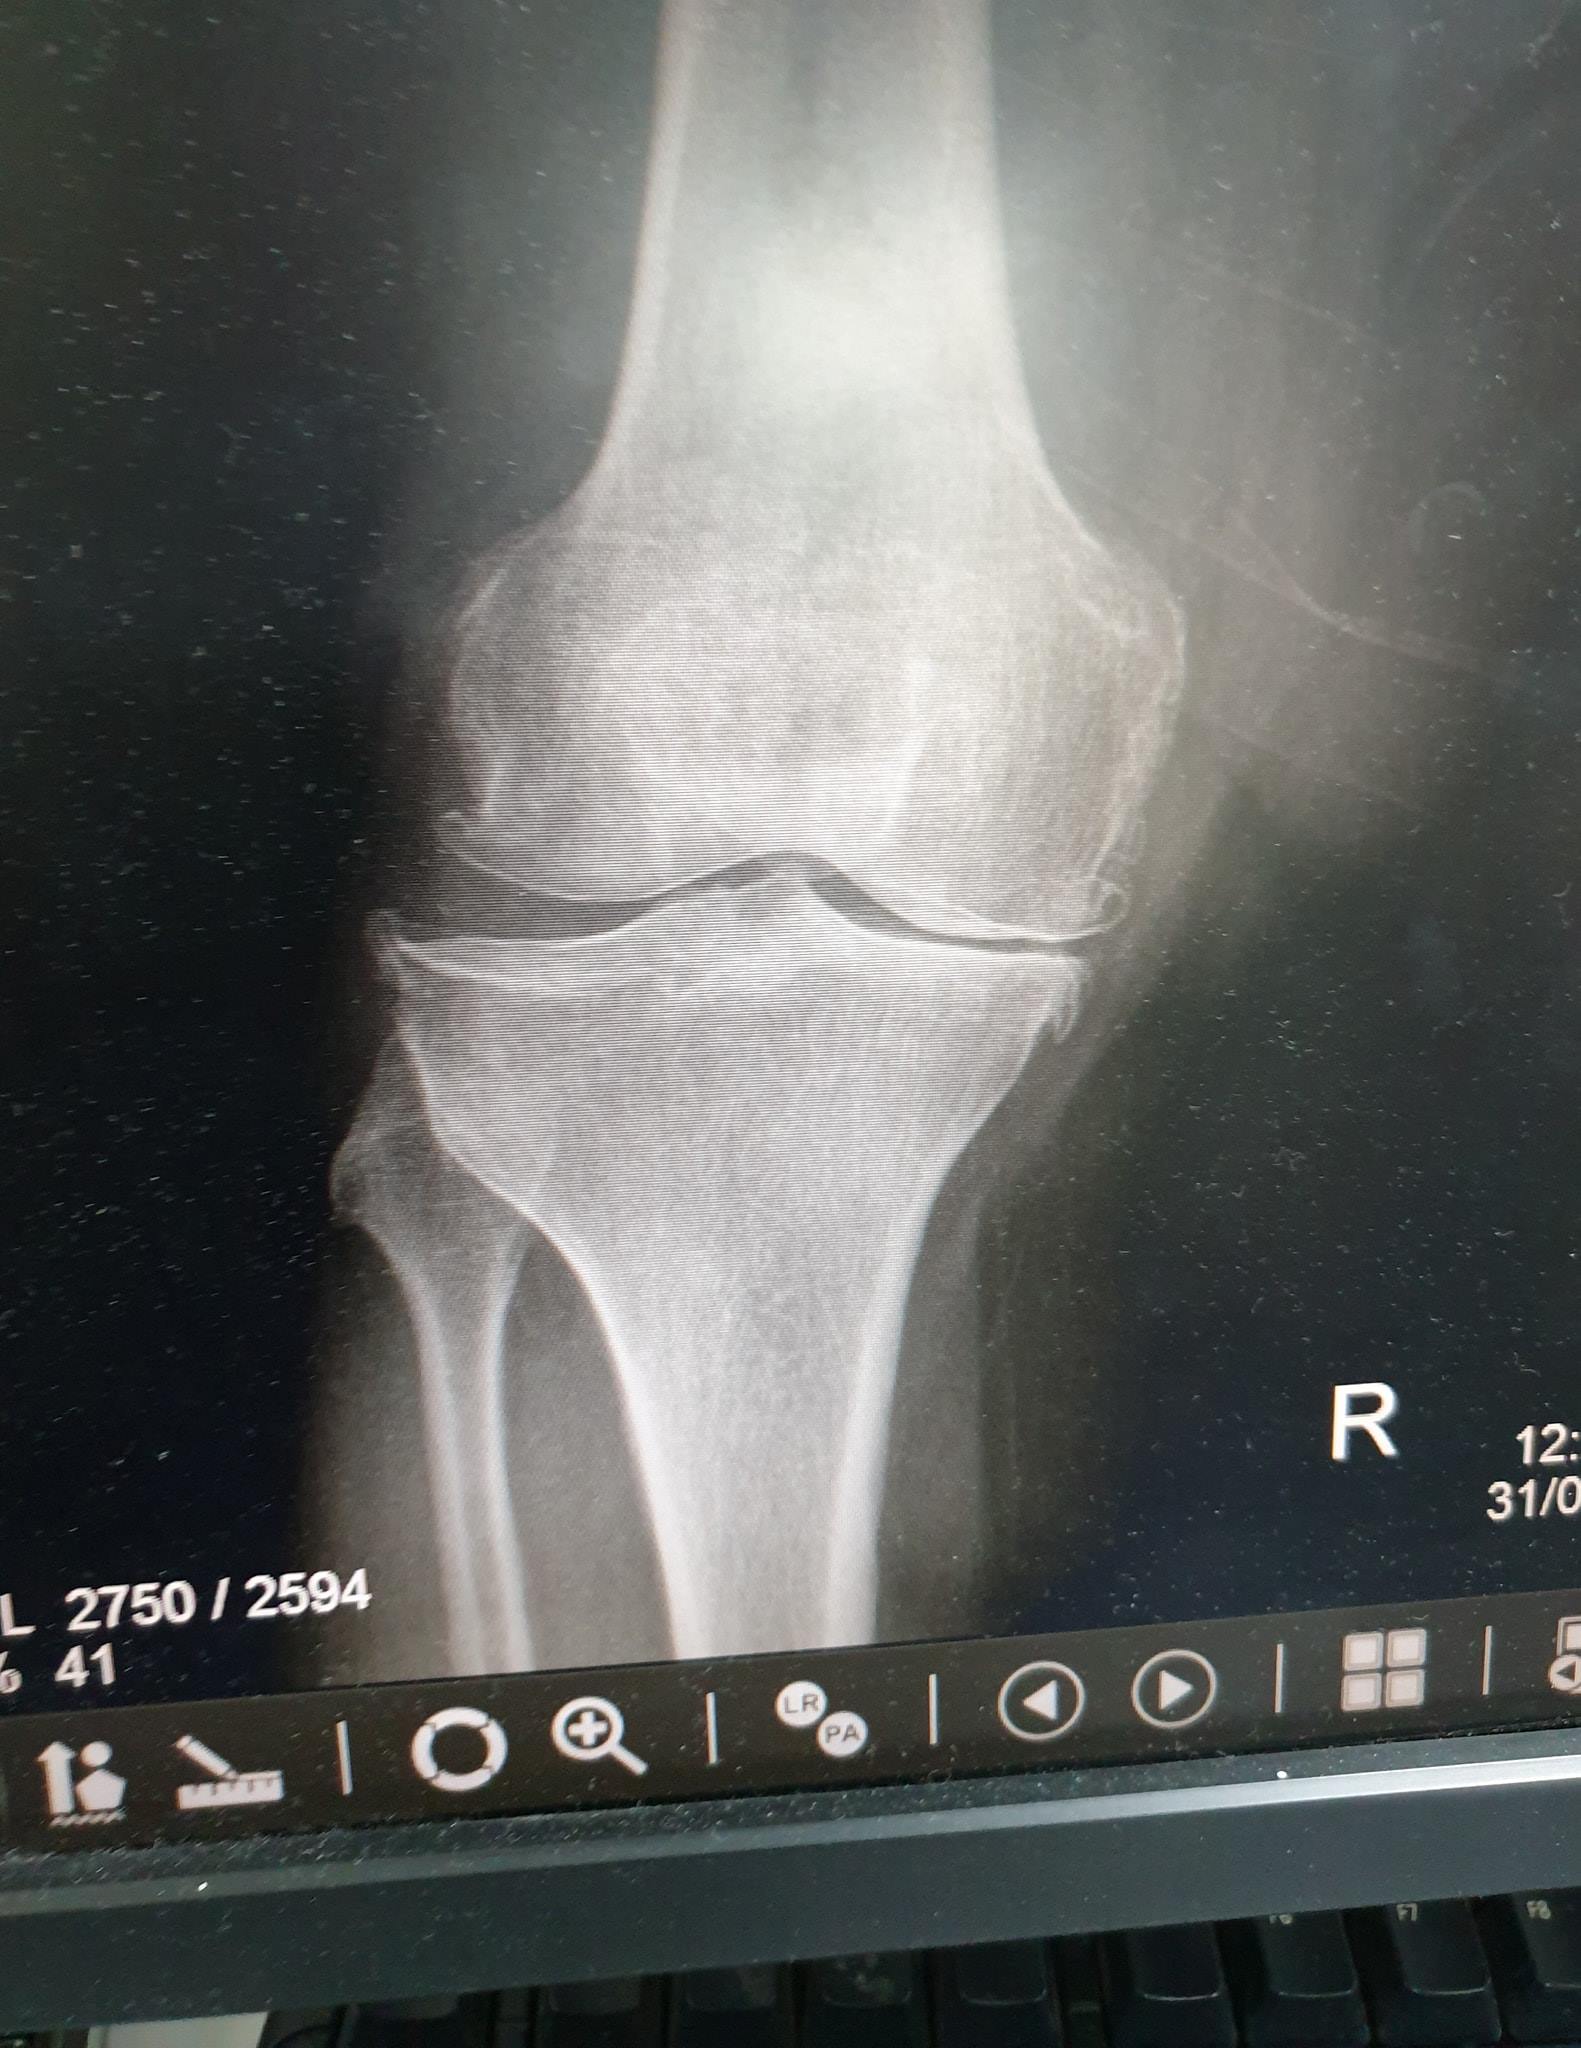

جراحة العظام والمفاصل

زراعة المفاصل الصناعية ورك و